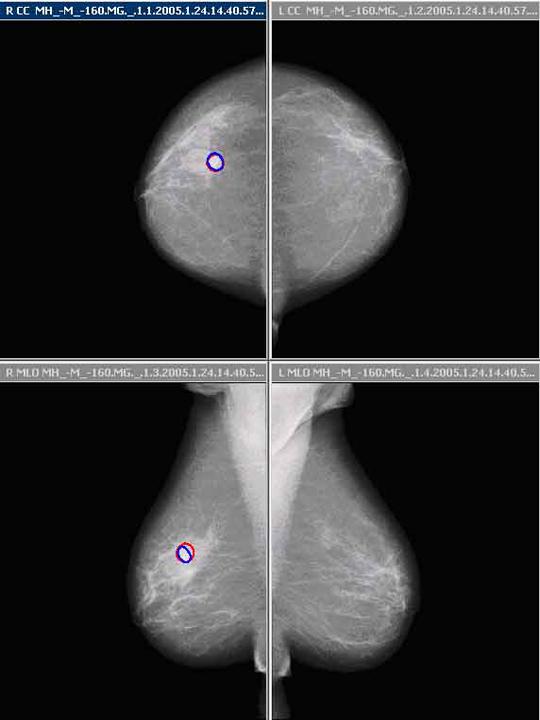

Whatever the individual situation, our innovations make screening and early diagnosis more reliable, efficient and comfortable than ever before - enabling early and therefore more effective therapeutic intervention.